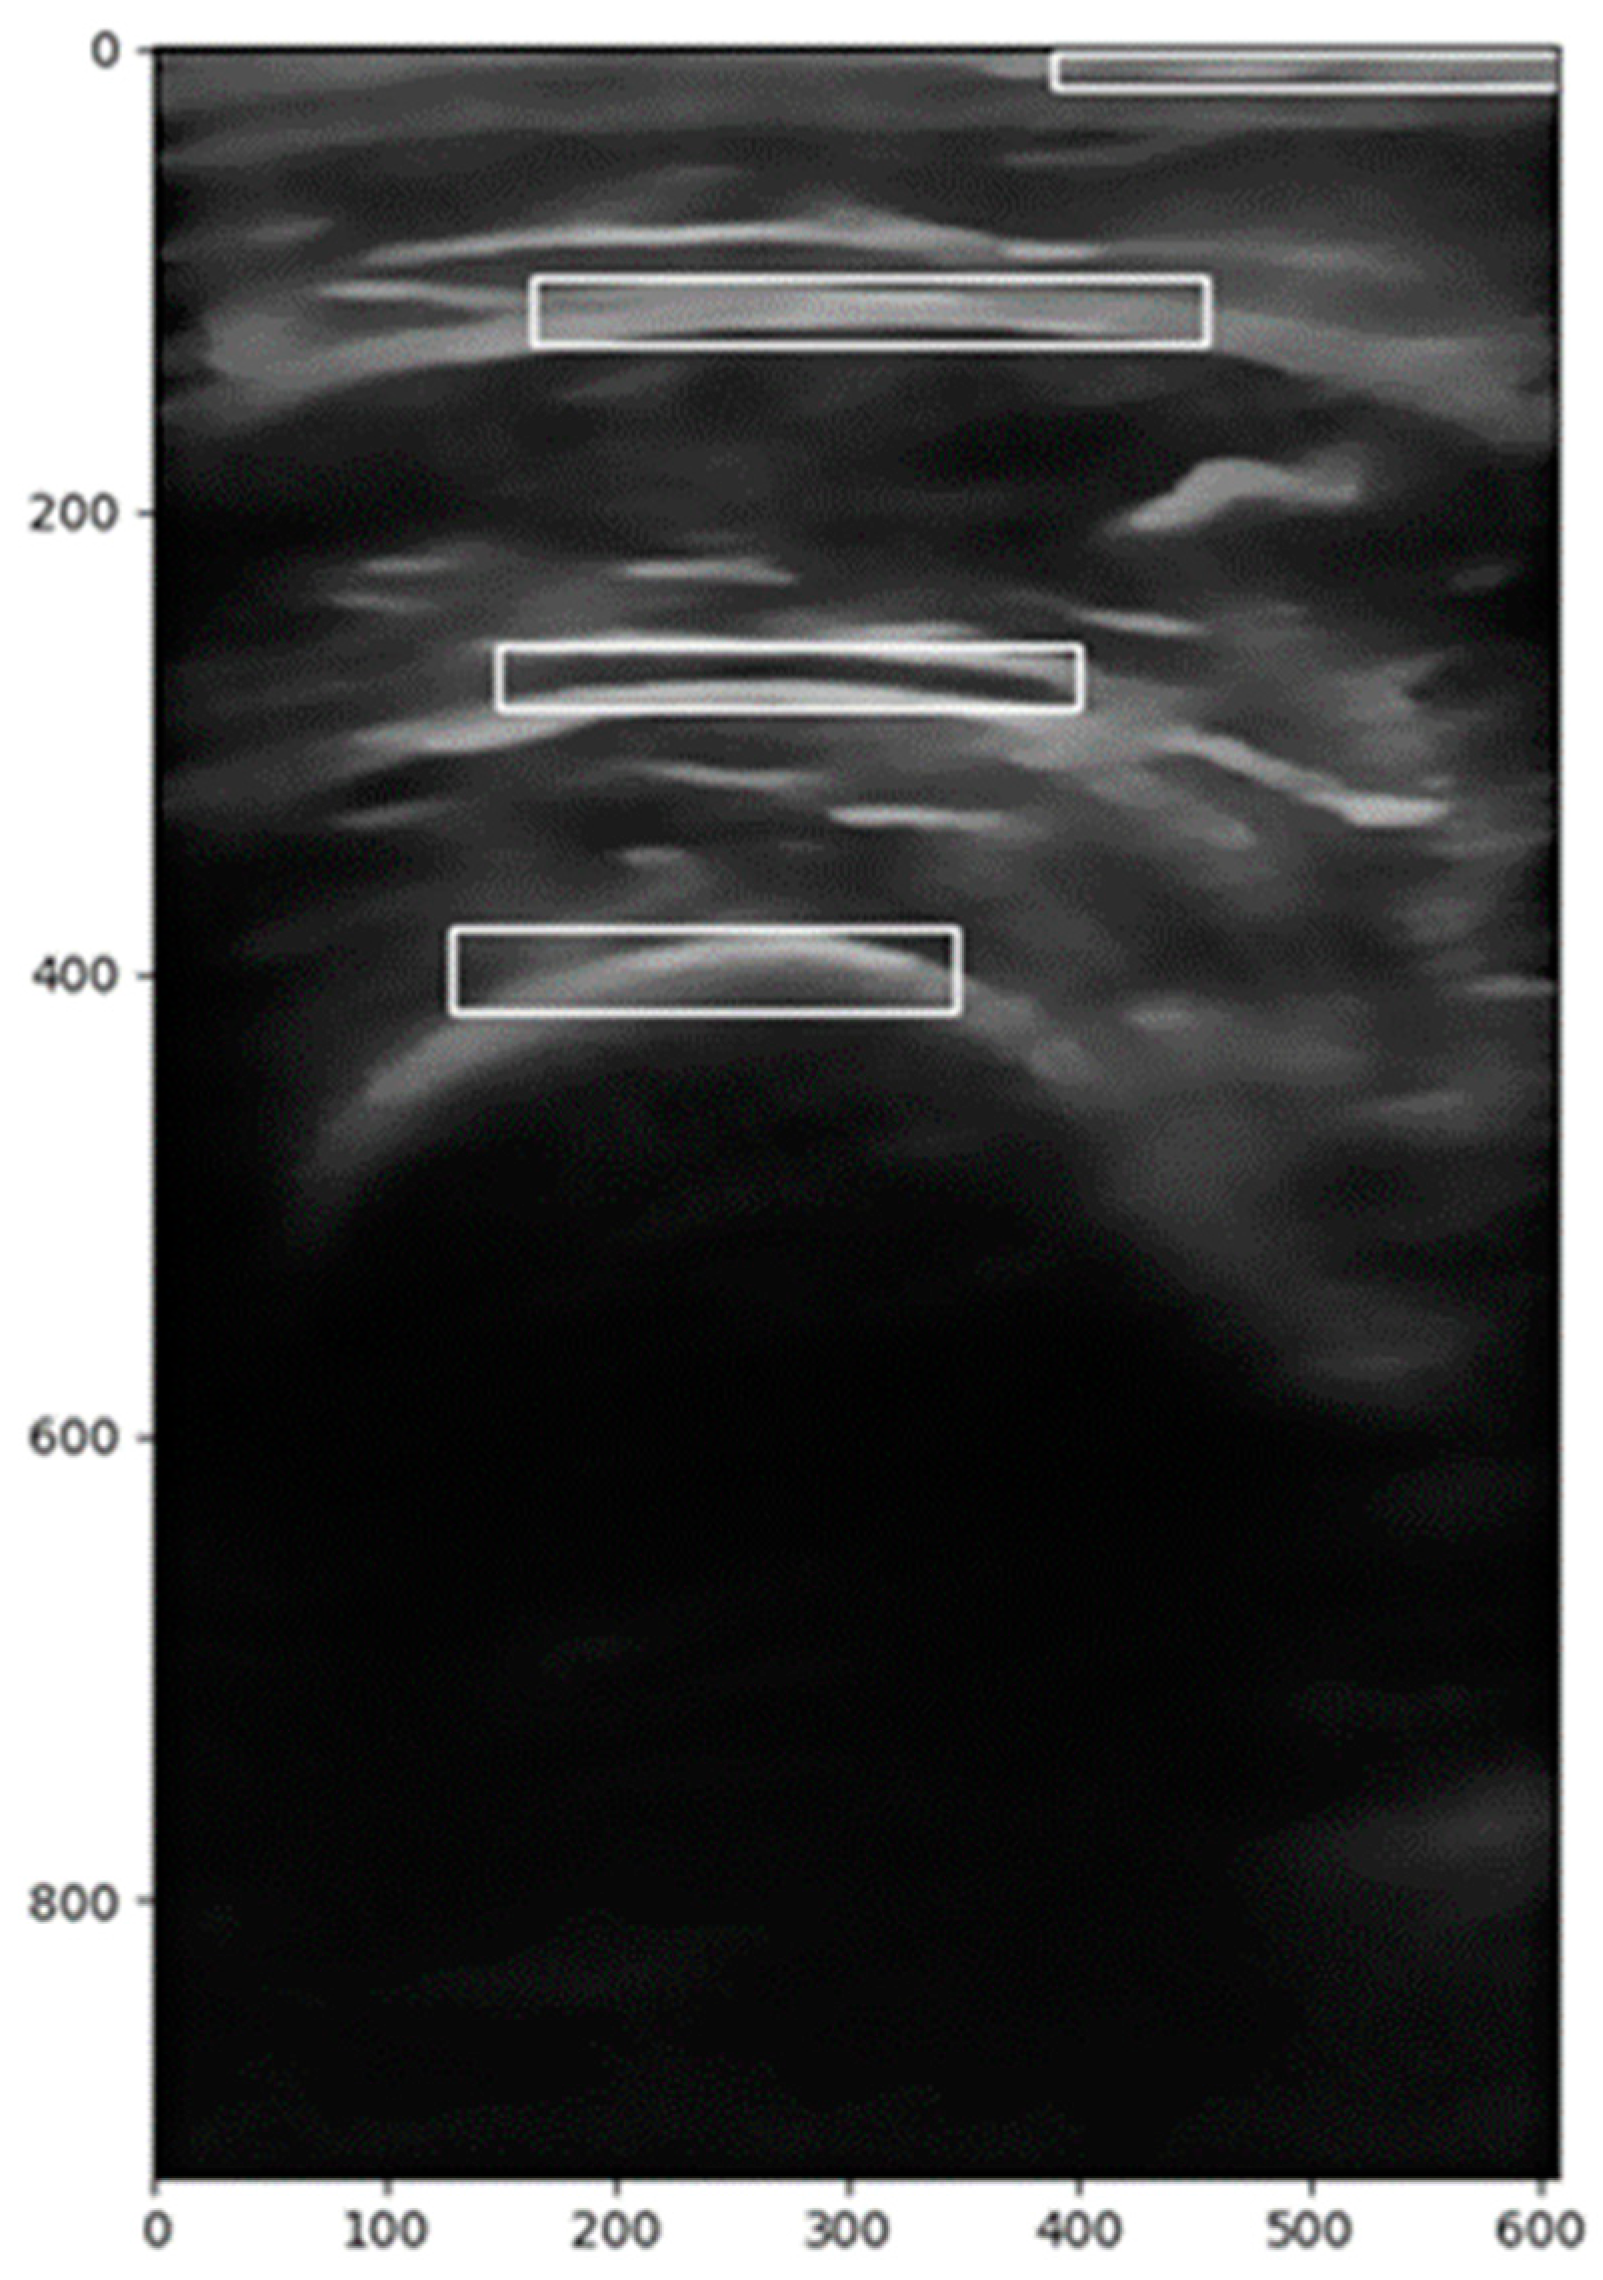

2.2.1. Image Segmentation

2.2.2. Image Correction

2.2.3. Calculation of the Region of Interest (ROI)

- A vertical range is selected to focus on the relevant anatomical structures.

- A backward scan (from the middle to the left) is performed to find the first column where pixel intensity exceeds a predefined threshold.

- A forward scan (from the middle to the right) is performed to find the last column where the pixel intensity is above the threshold.

- These two indices define the horizontal extent of the ROI.

- The midpoint of the image height is used as a reference.

- A downward scan is conducted to determine the lower boundary, which is the last row where significant pixel intensity is detected.

- An upward scan is performed to establish the upper boundary, where meaningful image data start.

2.2.4. Image Filtering

2.2.5. Image Transformation

2.2.6. Calculation of Distances and Areas